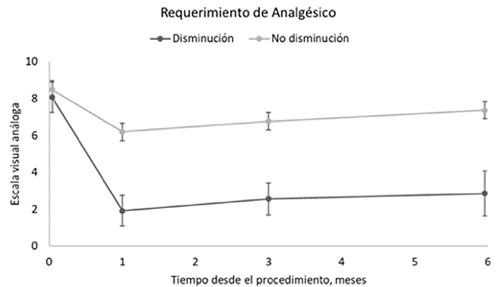

La Tabla 2 presenta el cambio medio en el dolor percibido relacionado con la disminución del requerimiento de analgésicos. En el 20 % de los pacientes que disminuyeron el requerimiento de analgésicos, la media de dolor en la línea de base fue de 8,1 puntos en la EVA; a un mes de la intervención mostraron descenso de 6,2 puntos (IC 95 %; -7,3, -5,0). Al sexto mes la diferencia de medias se redujo en aproximadamente un punto, manteniéndose estadísticamente significativa (-5,2; IC 95 %: -6,7, -3,8). En el 80 % de los pacientes que no tuvieron disminución de requerimiento de analgésicos, la media al primer mes fue de 2,3 puntos (IC 95 %: -2,8, -1,8) cerrándose para el sexto mes en 1,1 puntos (IC 95 %: -1,6, -0,6). En la Figura 1 se observan las diferencias de medias entre los meses 1, 3 y 6, siendo estadísticamente significativas solo en el último control. Estas diferencias no son explicadas por la edad, sexo o nivel socioeconómico de los pacientes.

Fig. 1. Promedio de dolor a los 1, 3 y 6 meses del procedimiento, según disminución en el requerimiento de analgésicos.